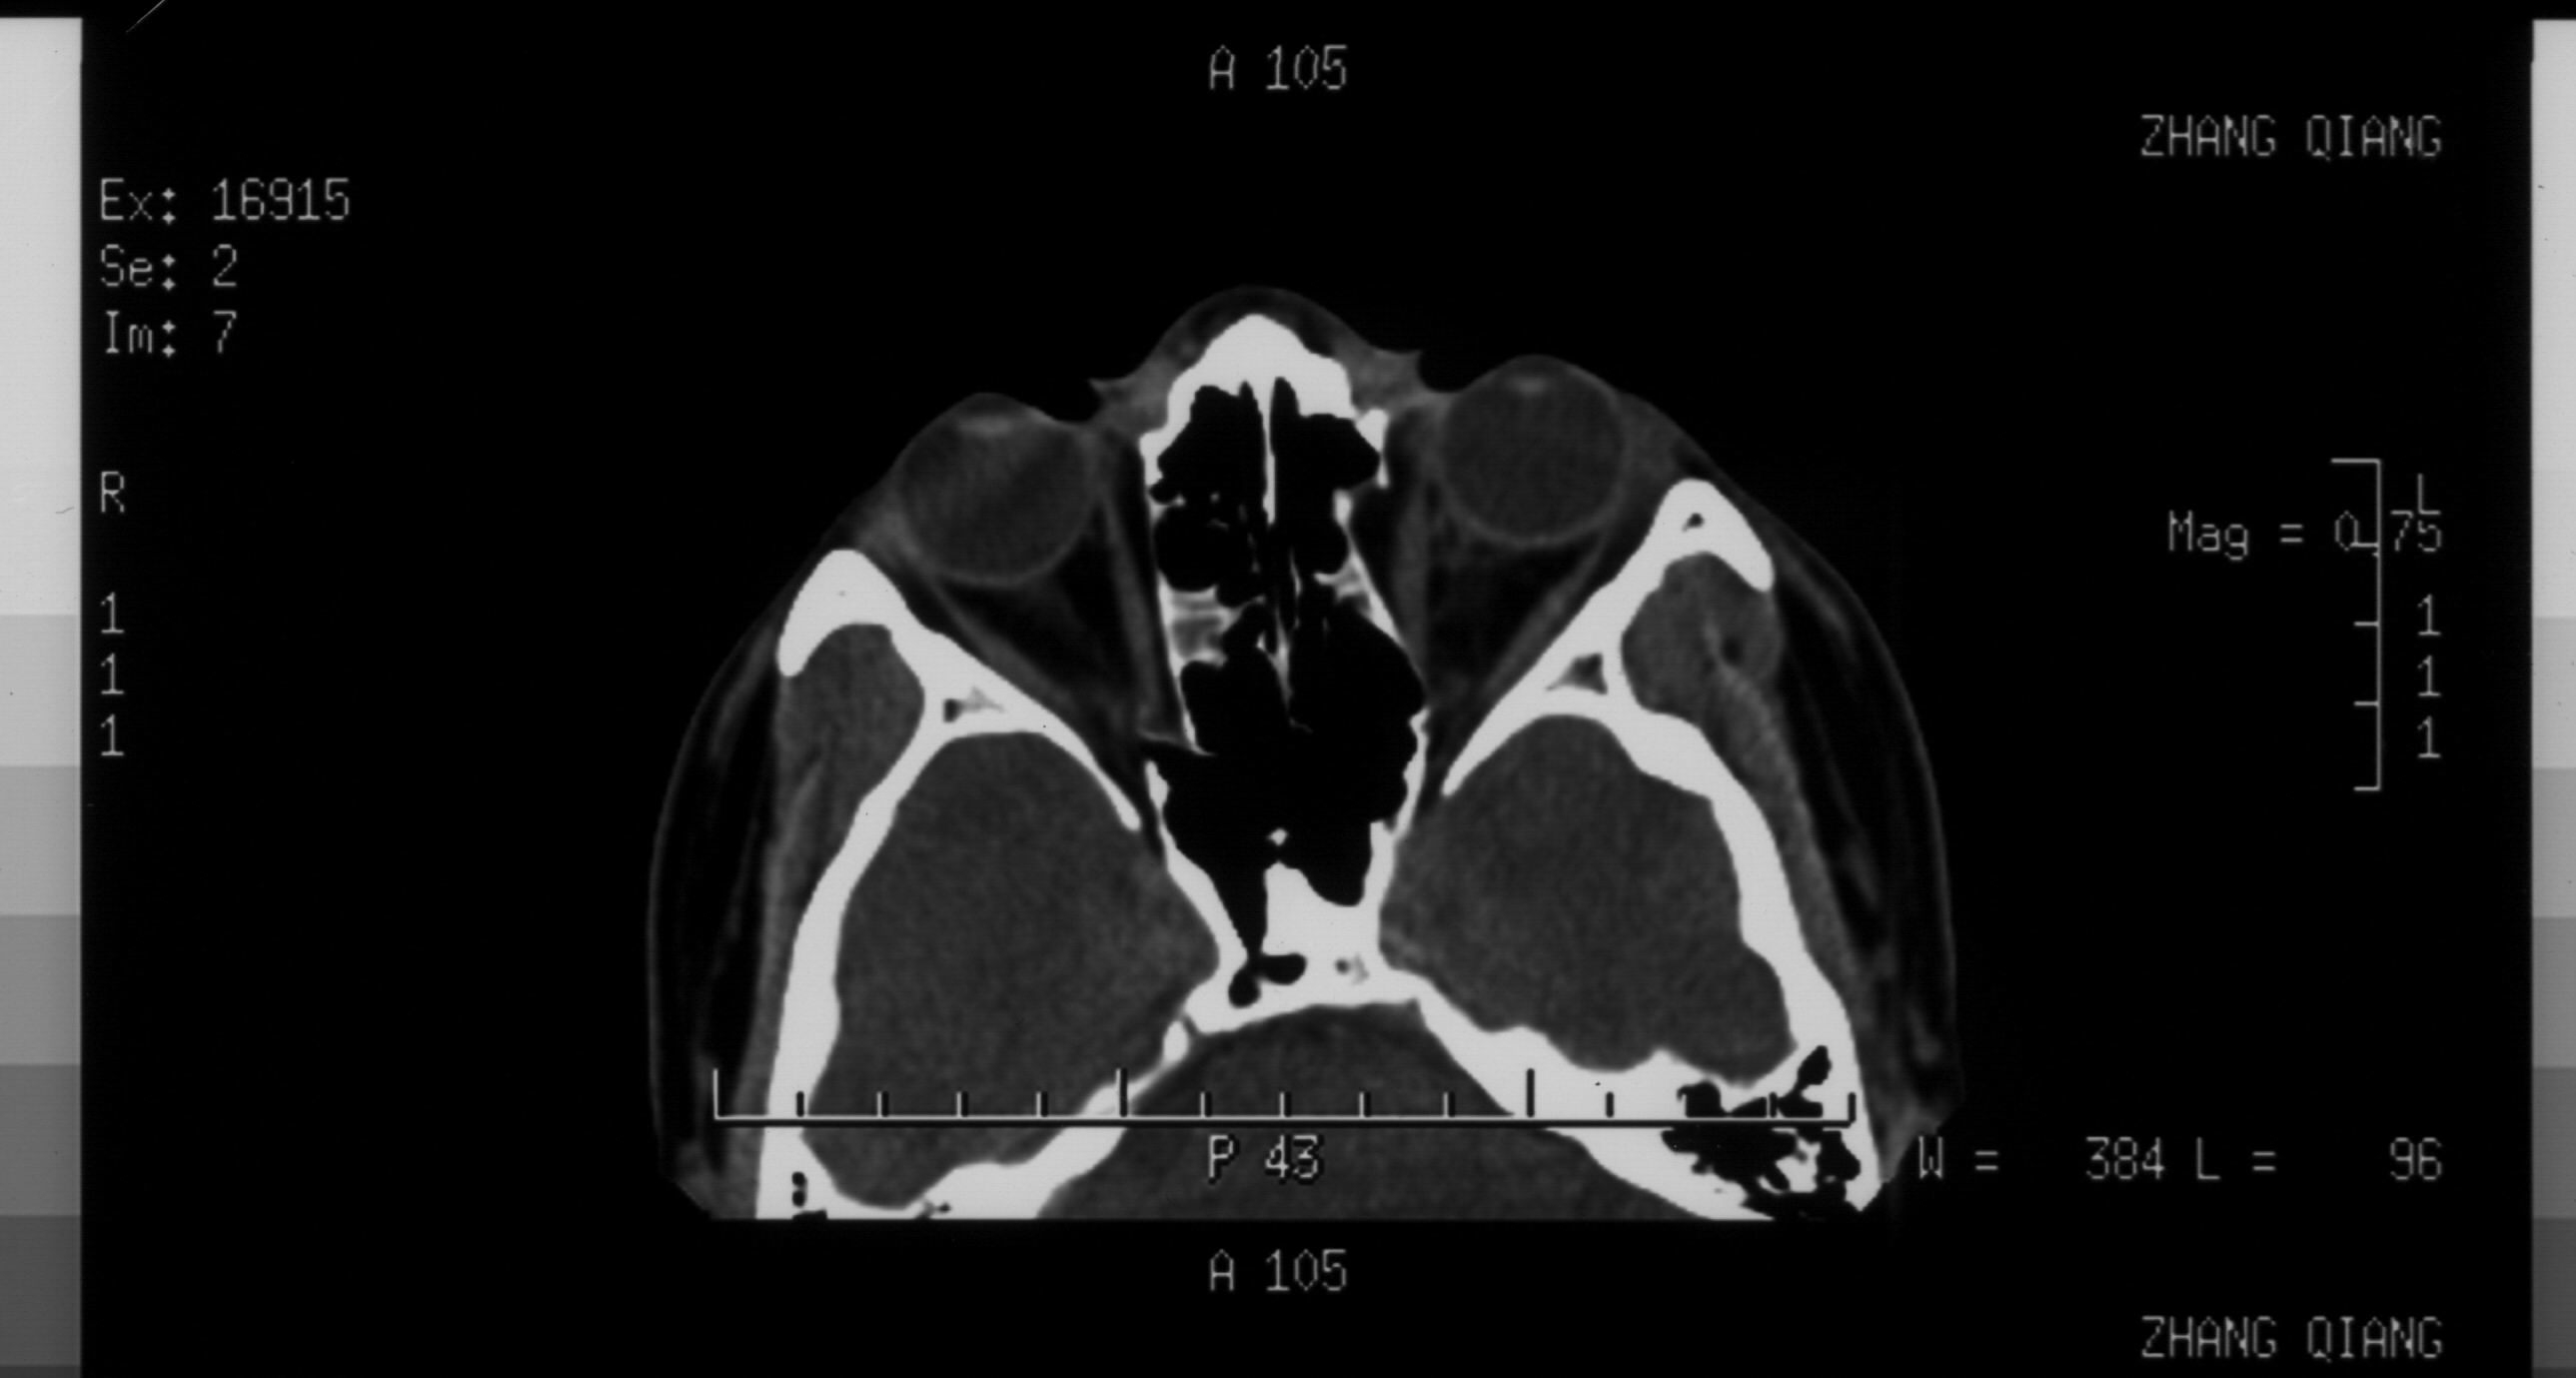

双眼拳击伤 双眼全方位复视

请解读一下ct片

你的CT片分析结果,至少有两点是可以确定的。1、双侧眼眶内侧鼻多发骨折 2、鼻骨骨折。

图588:可以看到箭头所示双侧纸样板骨折、移位。右侧骨折部位靠近眶尖,需要注意以下问题:1、通过视神经管薄层扫描除外视神经管骨折(结合临床视力和瞳孔反射)2、调出软组织窗,本人高度怀疑有内直肌近腱环处撕裂伤抑或是合并嵌顿。如同所述,则是急诊手术的绝对适应症,不能延误。左侧前部纸样板骨折明确,内直肌并未嵌顿在此处。而后部为可以骨折,希望结合上下层面及临床考虑,处理原则同前述。顺便提一下,右侧岩锥可疑裂缝,虽不能完全除外骨折,不过本人觉得正常骨缝的可能性更大。根据影像学经验,一般颅骨线状骨折的裂缝比较细小。另外,如果该部位出现骨折,则伴随临近部位的组织损伤和功能损害,果真如此,那就麻烦大了:首先,从神经科角度,颞叶出血、水肿或者该处脑膜下积血都会很严重。而此处又比邻海绵窦,可能的情况不用说了。第3、我们知道外展神经是颅内走行最长的颅神经。而在这个部位的解剖特点是边缘锐利,外展神经经此爬行,若发生外伤很容易伤及神经。所以,你要是真的想进一步了解这个区域,建议你行颅底薄扫加MRI。你自己权衡吧。

图560:箭头所示左侧鼻骨及鼻中隔骨折明确。另外,对于眼科医生应同时关注鼻泪管。通常这个部位容易被放射科大夫所忽视。